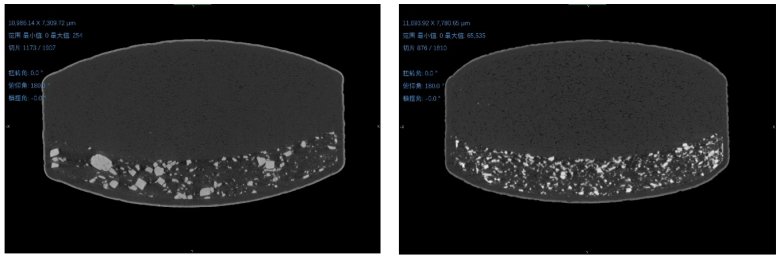

① 三維空間結(jié)構(gòu)形態(tài)

左圖為原研藥,右圖為仿制藥